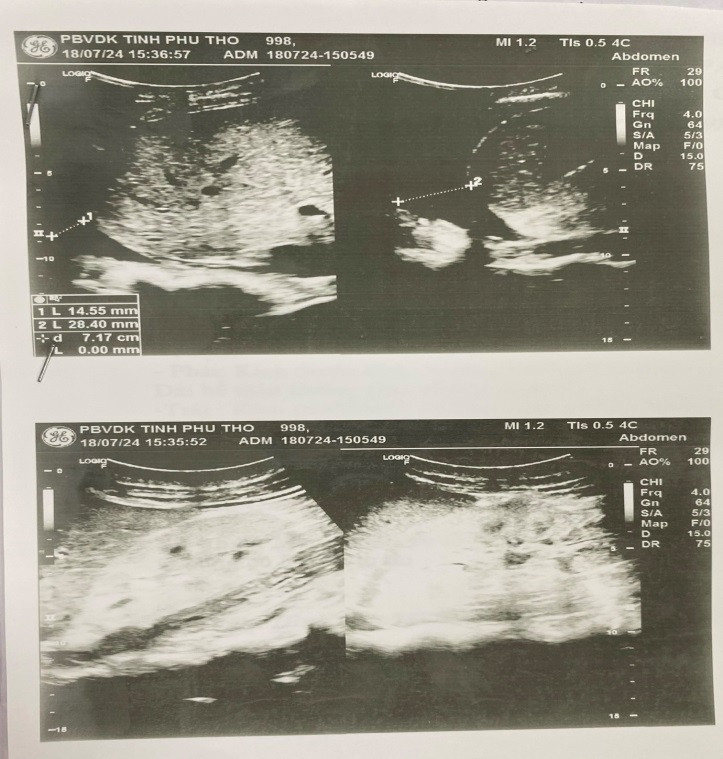

Tại Bệnh viện đa khoa tỉnh Phú Thọ, sau khi khám lâm sàng và làm các xét nghiệm, siêu âm tổng quát đã cho thấy thấy có thiếu máu HC 3,24 T/L, HST 90 g/l; huyết áp cao 180/100 mmHg; chức năng thận suy giảm nhiều Ure 28,28 mmol/L, creatinin 810,9 mmol/L; trên siêu âm 2 thận đã teo nhỏ, có dịch ổ bụng và dịch màng phổi hai.

| Kết quả siêu âm cho thấy 2 thận người bệnh đã teo nhỏ, có dịch ổ bụng và dịch màng phổi hai bên - Ảnh: BVCC |